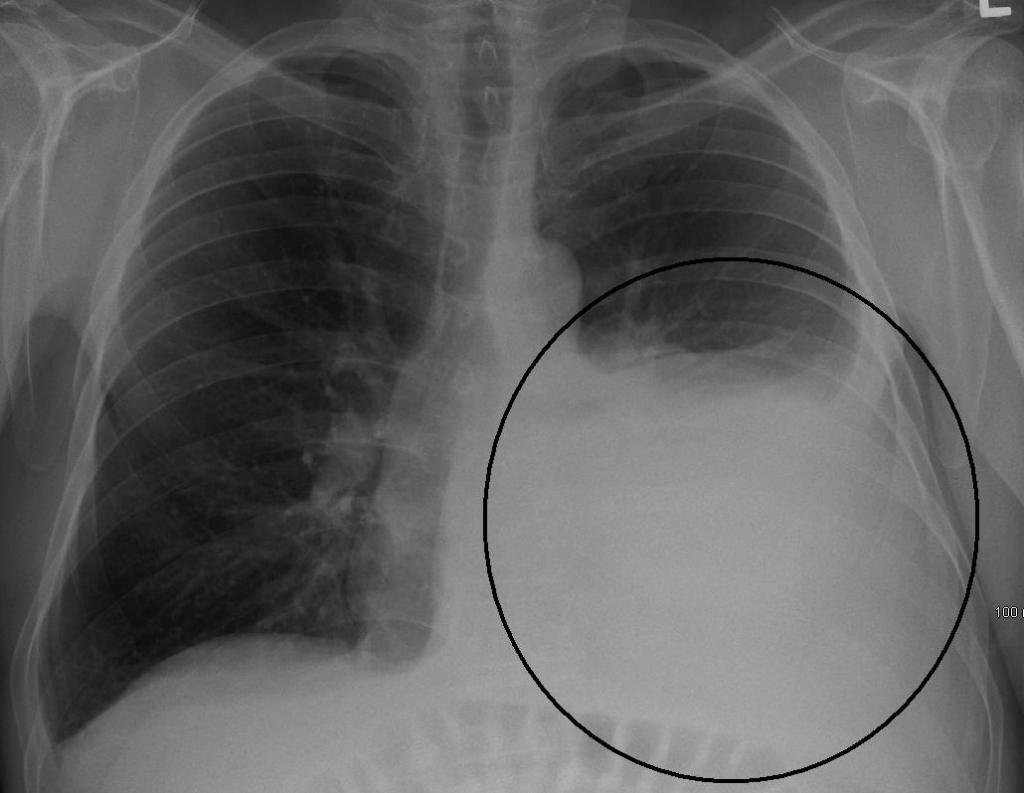

На рентгенографии симптомы выпотного плеврита легких отображаются как интенсивное однородное затемнение в нижних долях органа. Высокое стояние диафрагмы наблюдается при небольшом скоплении жидкости. Средостение смещено к здоровому легкому. При выполнении снимка в латеропозиции (больной ложится на бок) происходит горизонтальное смещение экссудата.

Не выпотной плеврит легких на снимке проявляется интенсивными тенями неоднородной структуры, синусы не определяются. Подвижность плевры резко ограничена.